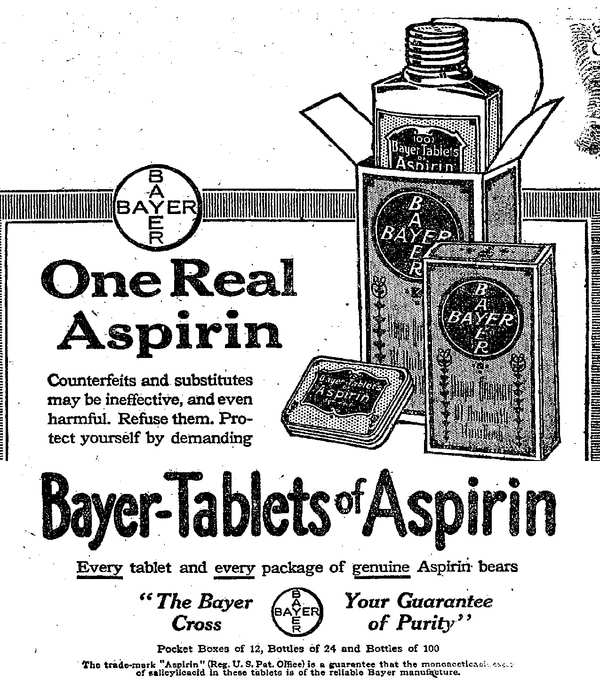

1897年8月10日

为了减轻父亲的关节炎疼痛,药剂师Felix Hoffmann将稳定的乙酰化水杨酸与乙酸混合,获得了阿司匹林。在成功地完成了数个大规模临床试验后,Hoffmann所就职的公司----拜耳公司----开始在全球市场上销售这个药物。尽管阿司匹林的治疗适应证发生了很多变化,但它的发现依然是医学和药理学史上的里程碑式事件。

1988年1月28日

有研究发现,325 mg阿司匹林的隔天使用可以大幅度(近1/2)降低致死性/非致死性心肌梗塞的发病率。